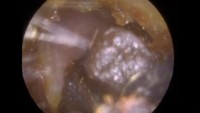

Sepertinya ini terdapat infeksi sehingga warnanya menghitam. (Foto: YouTube)